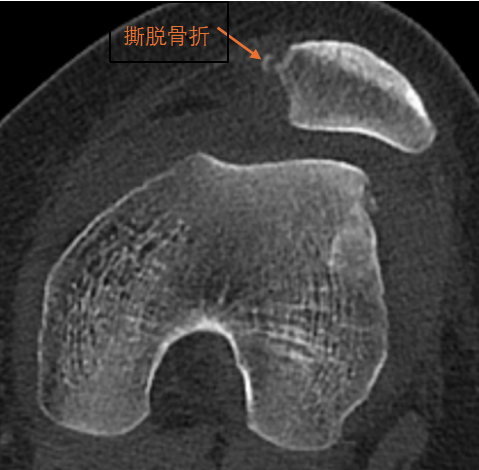

2、CT:

可以更准确地反映髌股关节位置情况,可以发现合并的髌骨和股骨髁撕脱骨折,是髌骨脱位重要检查手段。